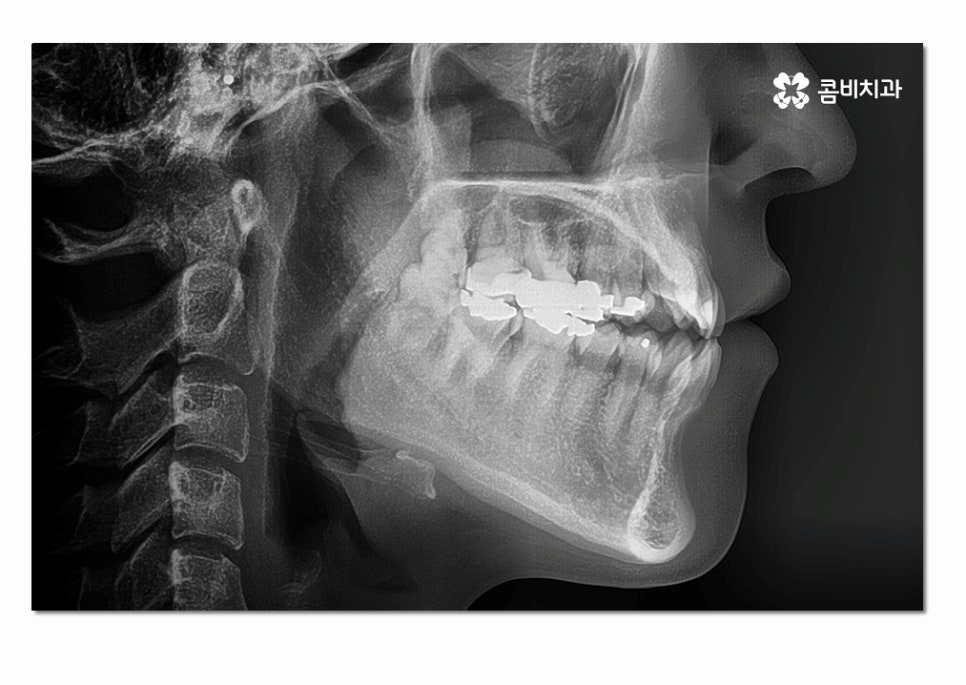

위 환자분의 경우에는 이미 성인이 된 상태에서 3급 부정교합

치료를 진행하게 된 사례라고 볼 수 있는데요.

이미 턱뼈의 성장이 끝난 성인의 경우 성장 조절이 불가능하기 때문에

부정교합 치아교정을 진행하면서 발치를 해야 하거나

치아교정과 양악 수술을 함께 병행해야 하는 경우가 있어요.

하지만 요즘은 의술의 발달로 비수술, 비발치를 통해서

좋은 결과를 얻는 사례도 많기 때문에 처음부터 두려워하기보다는

충분한 검진을 받아보시고 전문의의 소견에 따라 판단하셔야 할 거예요.

위 환자분의 경우에는 클리피씨 교정 장치를 통해서 치료가 진행되었으며

발치와 수술 없이 3급 부정교합을 개선한 사례라고 할 수 있어요.